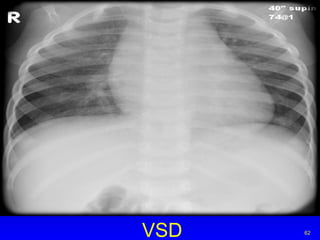

VSD